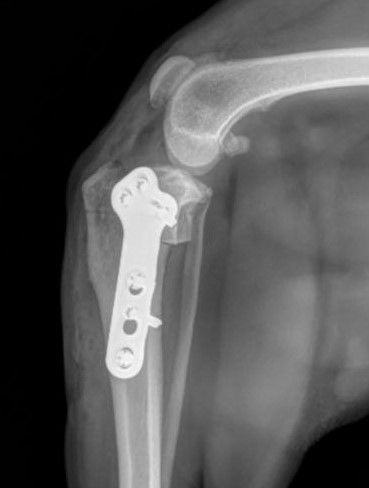

TPLO Surgery

Why do patients need Rehabilitation after TPLO (tibial plateau leveling osteotomy) surgery? The stifle is stable! The TPLO has become a common procedure to restore mechanical stability to cruciate-deficient stifles. However, the TPLO does not address all the common sequelae that develop as a result of cruciate disease: